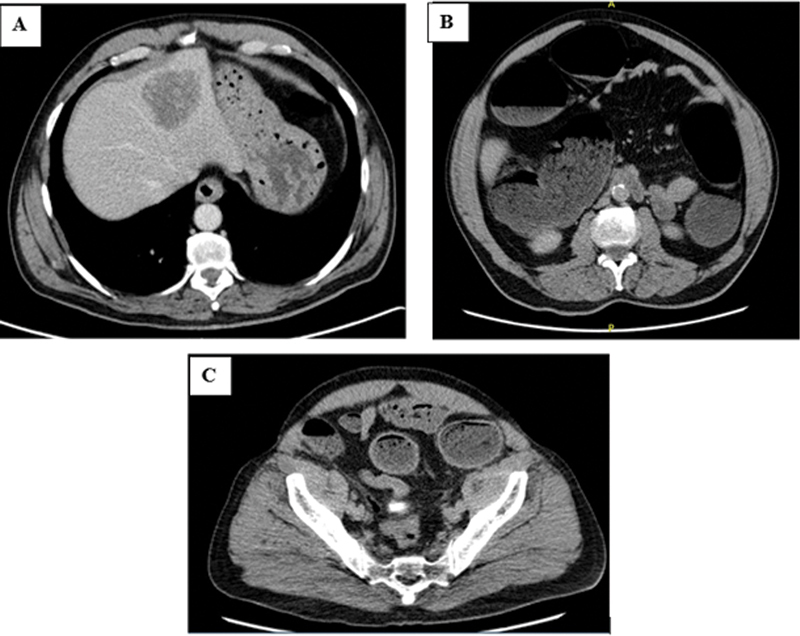

Colonic obstruction is reported in 85% of emergency colorectal surgery for cancer. Colonic ischemia, however, is a rare entity and is found in 5% of these emergency cases. We herein present the case of a 72-year-old man presenting with signs and symptoms of obstruction and was found to have an obstructive sigmoid cancer. A first urgent laparotomy showed small bowel ischemia, for which small bowel resection and large bowel decompression were done without tumor resection. Postoperatively, the patient transiently improved, then deteriorated in few days, and a second urgent laparotomy showed a large bowel ischemia proximal to the mass. The treatment for patients with colon cancer with suspected colonic ischemia should be emergency laparotomy with long abdominal incision, carefully exploring the whole length of the small and large bowel. Despite large bowel decompression, a secondary colonic ischemic event should be suspected in case of deterioration.

Abstract Image